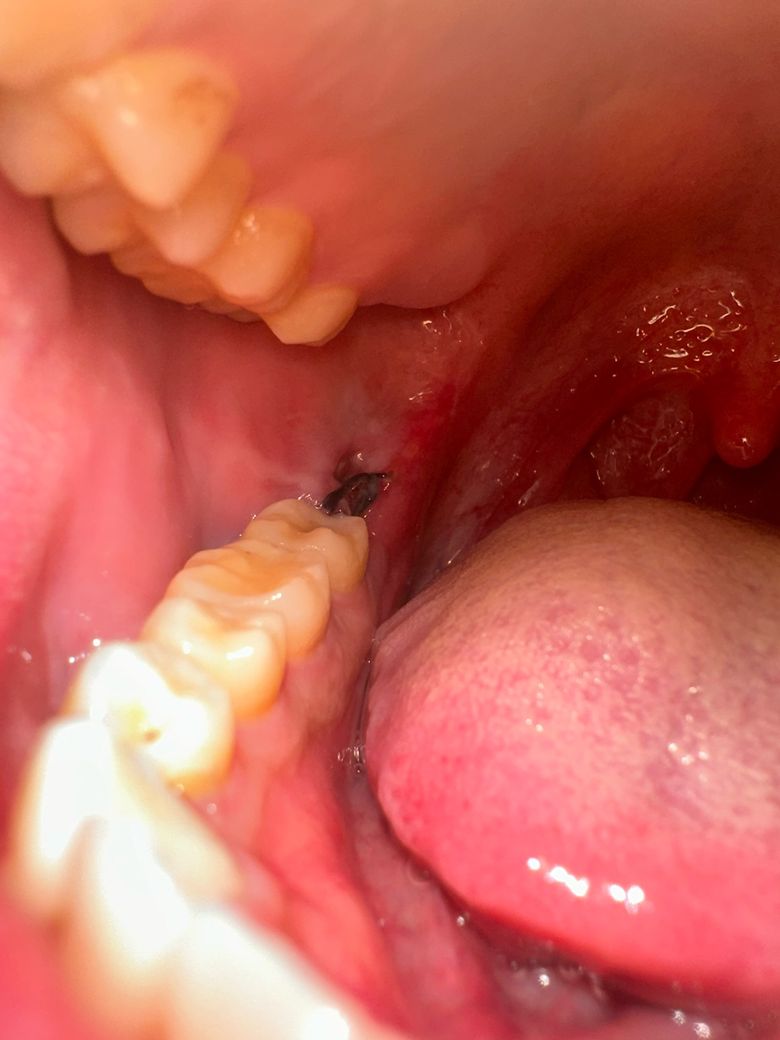

사랑니 아래 부분매복사랑니 발치 4일차

사랑니 아래 부분매복사랑니 발치4일차입니다.

다름이 아니라 혈병이 완전히 다떨어진거 같아서 글을 남겨봅니다.

드라이소켓은 아니겠지요?..참고로 3일차부터 가벼운 음주와 흡연을 했습니다

사진은 첨부해드리겠습니다.(첫번째 3일차, 두번째 4일차)

사진상으로 문제는 없어 보입니다. 아직은 상처가 다 아물지 않아서 그러는거니 크게 걱정하지 않으셔도 될것같습니다.

1. 피떡은 원래 발치 후 1~2일차에 흡수되어 잇몸 회복에 필요한 조직으로 치환됩니다 지금 안보이는게 맞습니다